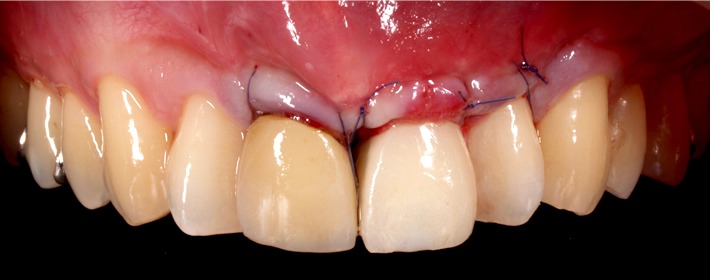

自家骨をブロックで採取して移植(ベニアグラフト)し、骨の厚みを増します。

最善の位置・角度でインプラント埋入